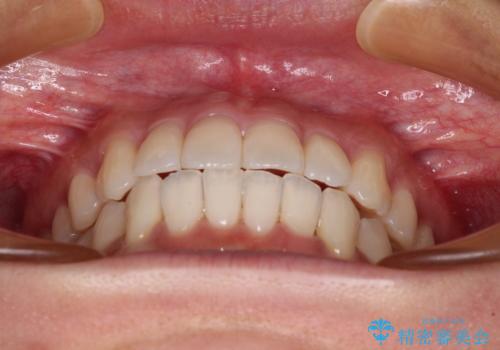

捻れた前歯をできるだけ短期間で 表側のワイヤー矯正

- 上下前歯のねじれを気にして来院された患者様です。

ワイヤー矯正でもマウスピース矯正でも対応可能でしたが、マウスピース矯正の自己管理が面倒であること、上顎前歯の捻転が著しいことから、ワイヤー矯正での治療を希望されました。

日々前歯の捻れが解消されていくので、歯の動きを楽しみながら矯正治療を進めることができました。